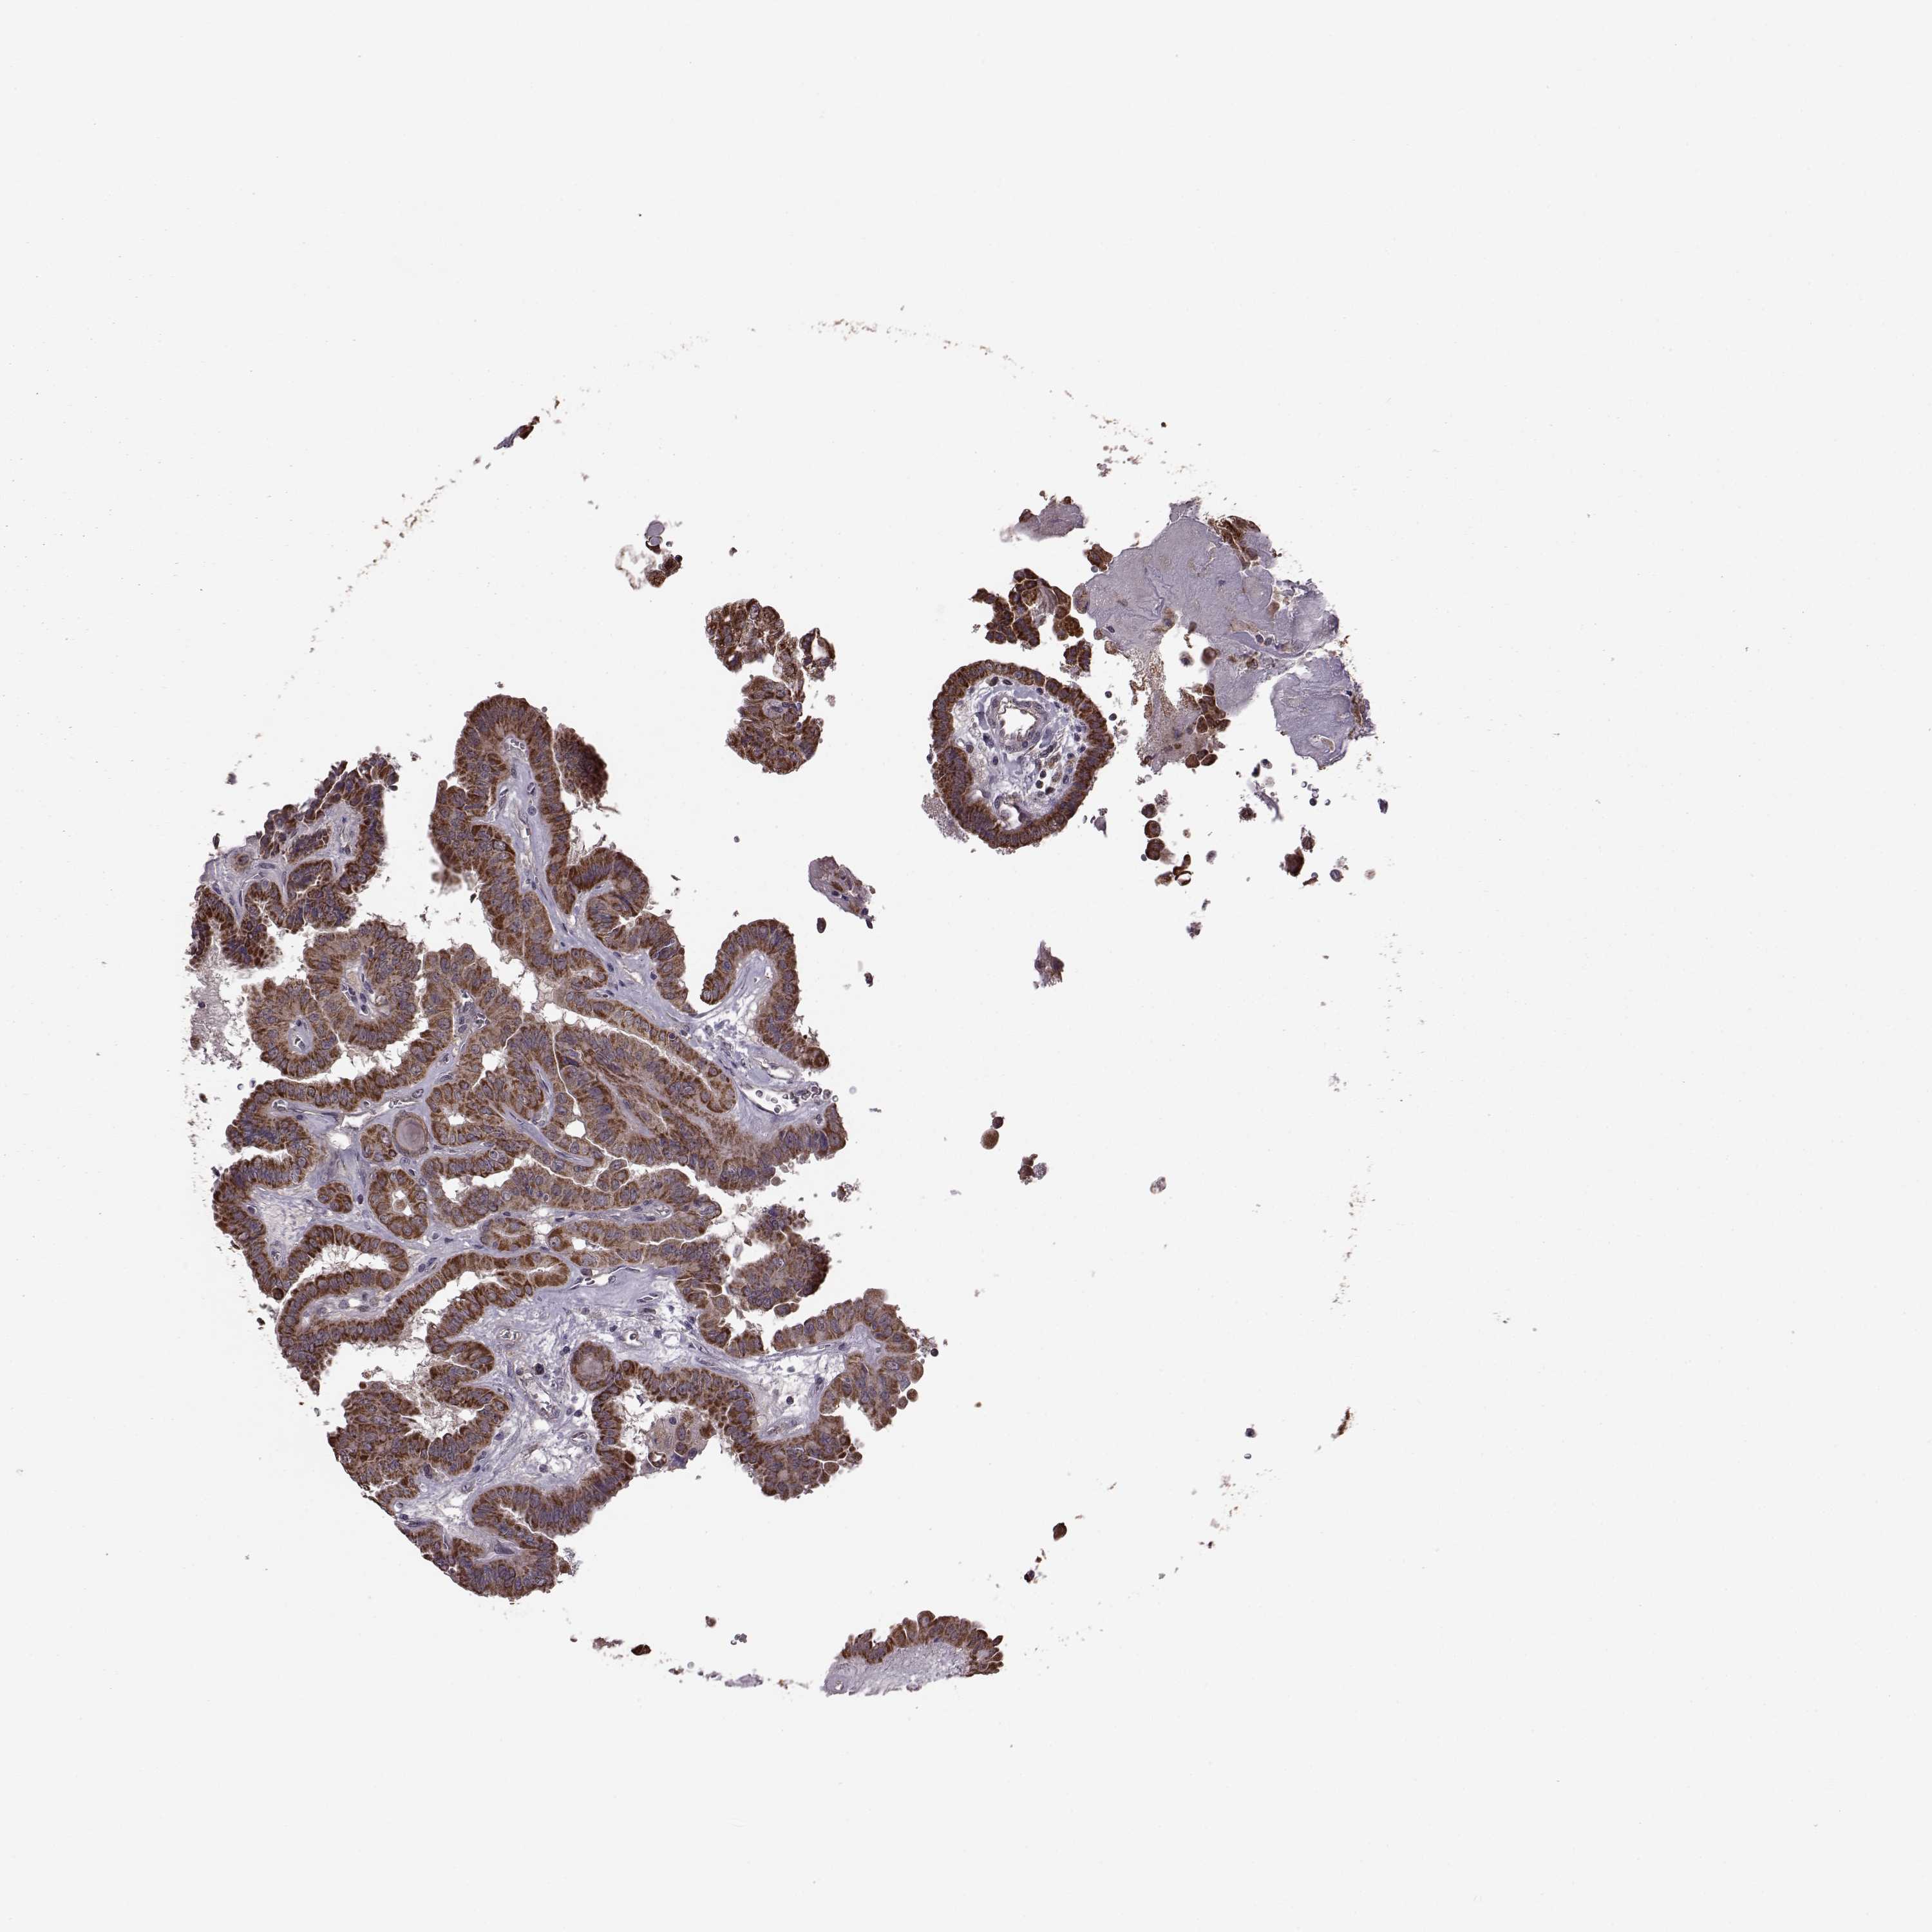

THYROID CANCER - Protein expressioni

A mouse-over function shows sample information and annotation data. Click on an image to view it in a full screen mode. Samples can be filtered based on level of antibody staining by selecting one or several of the following categories: high, medium, low and not detected. The assay and annotation is described here.

Note that samples used for immunohistochemistry by the Human Protein Atlas do not correspond to samples in the TCGA dataset.

Antibody stainingi

Antibody staining in the annotated cell types in the current human tissue is reported as not detected, low, medium, or high, based on conventional immunohistochemistry profiling in selected tissues. This score is based on the combination of the staining intensity and fraction of stained cells.

Each image is clickable and will lead to virtual microscopy that enables deeper exploration of all samples and also displays staining intensity scores, fraction scores and subcellular localization as well as patient and tissue information for each sample.

Antibody HPA072672

Staining

High

Medium

Low

Not detected

Intensity

Strong

Moderate

Weak

Negative

Quantity

>75%

75%-25%

<25%

None

Location

Nuclear

Cytoplasmic/membranous

Cytoplasmic/membranous,nuclear

Papillary adenocarcinoma, NOS

Follicular adenoma carcinoma, NOS